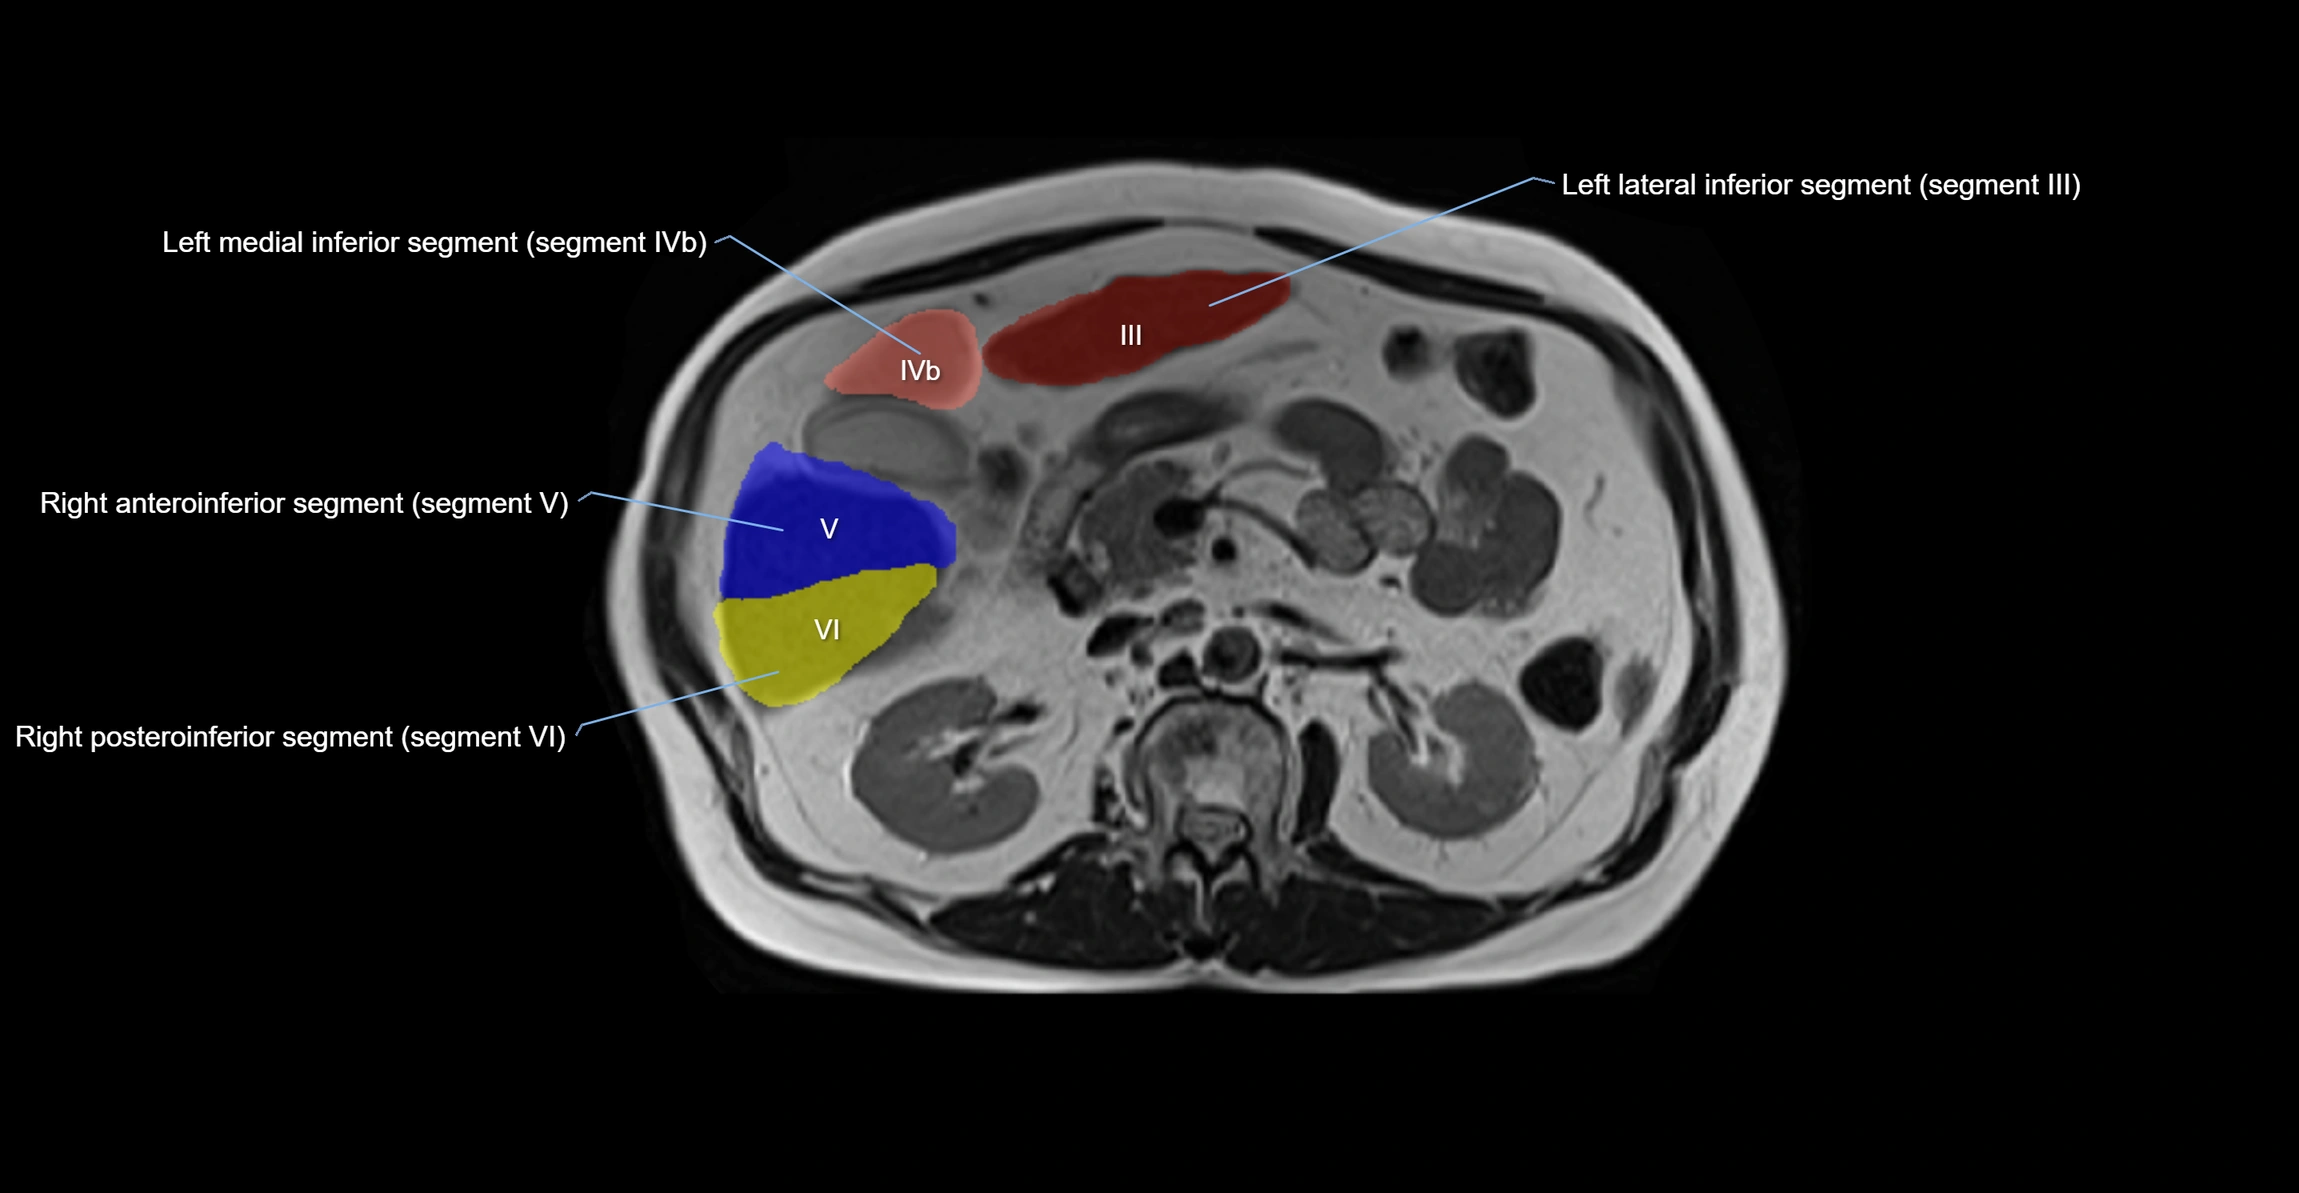

The caudate lobe of the liver is a distinct anatomical subdivision of the liver, designated as segment I in Couinaud’s classification. It lies on the posterior surface of the liver, between the fissure for the ligamentum venosum (left boundary) and the groove for the inferior vena cava (IVC) (right boundary). Superiorly, it is related to the posterior liver surface, and inferiorly it is separated from the left lobe by the porta hepatis.

The caudate lobe is unique because it receives dual portal venous and arterial inflow from both the right and left portal veins and hepatic arteries. It also has independent venous drainage directly into the IVC via multiple small hepatic veins, unlike other lobes that drain through the three main hepatic veins.

• Segment I (Couinaud classification)